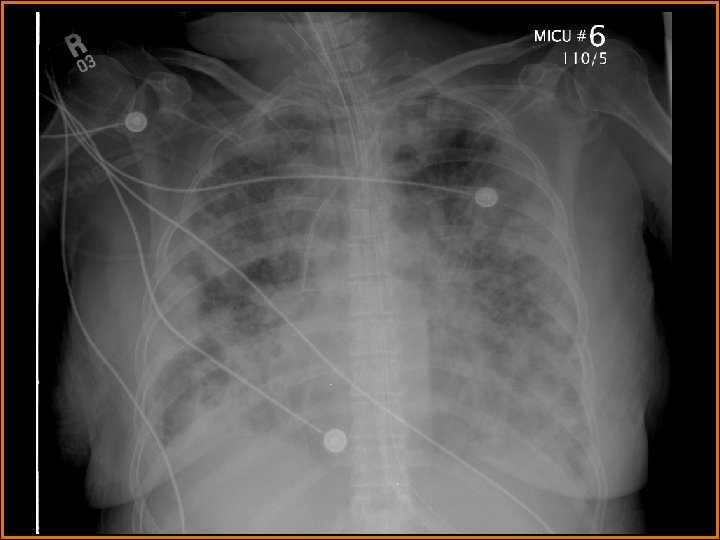

Case History 64 -year-old female presents with fever. Two serial portable chest radiographs are provided.

Findings and Differentials Chest x-ray findings: Multiple bilateral patchy alveolar opacities are seen diffusely. Many of these opacities are nodular, and some are cavitary. There are bilateral pleural effusions. Retrocardiac opacification is seen and may be secondary to the effusions and/or the airspace disease. The life support lines and tubes are unremarkable. A large lucency projects over the right hemidiaphragm. What would you like to do next? Think about your answer before advancing to the next slide.